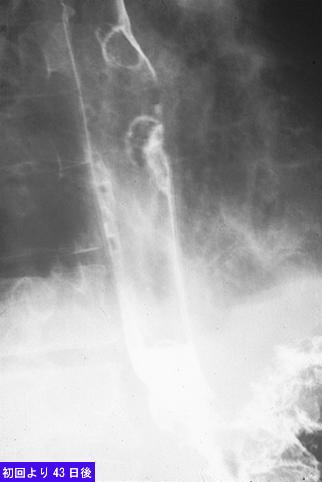

Cáncer Avanzado de Estómago tipo 4, que se diagnosticaban múltiples metástasis al esófago

Tokyo Pref., Centro Nacional de curaciones de Cáncer, Hospital Central y Centro Kyusyu de Curaciones de Cáncerc

Tumor Epitelial Maligno/Adenocarcinoma

esófago/mas de dos

Rayos X

15 - 19